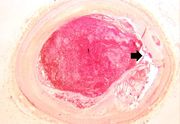

| 16:27, 19 August 2013 | IPLab4MuralThrombus2.jpg (file) | 39 KB | Seung Park | This is a low-power photomicrograph of the thrombus (1) attached to the myocardium (2). | 1 | |